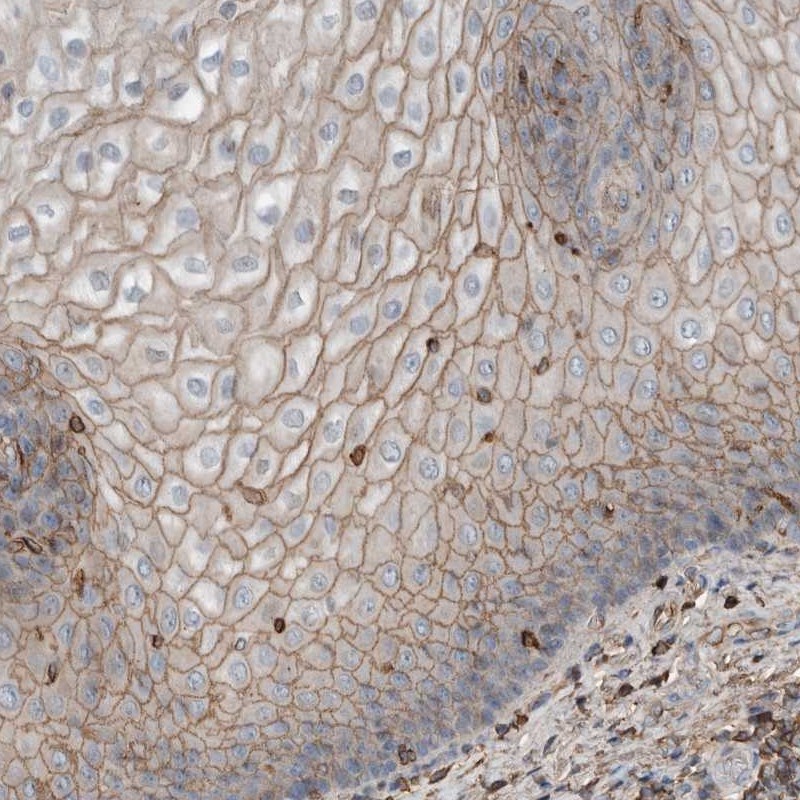

Immunohistochemical staining of human esophagus shows moderate membranous positivity in squamous epithelial cells.